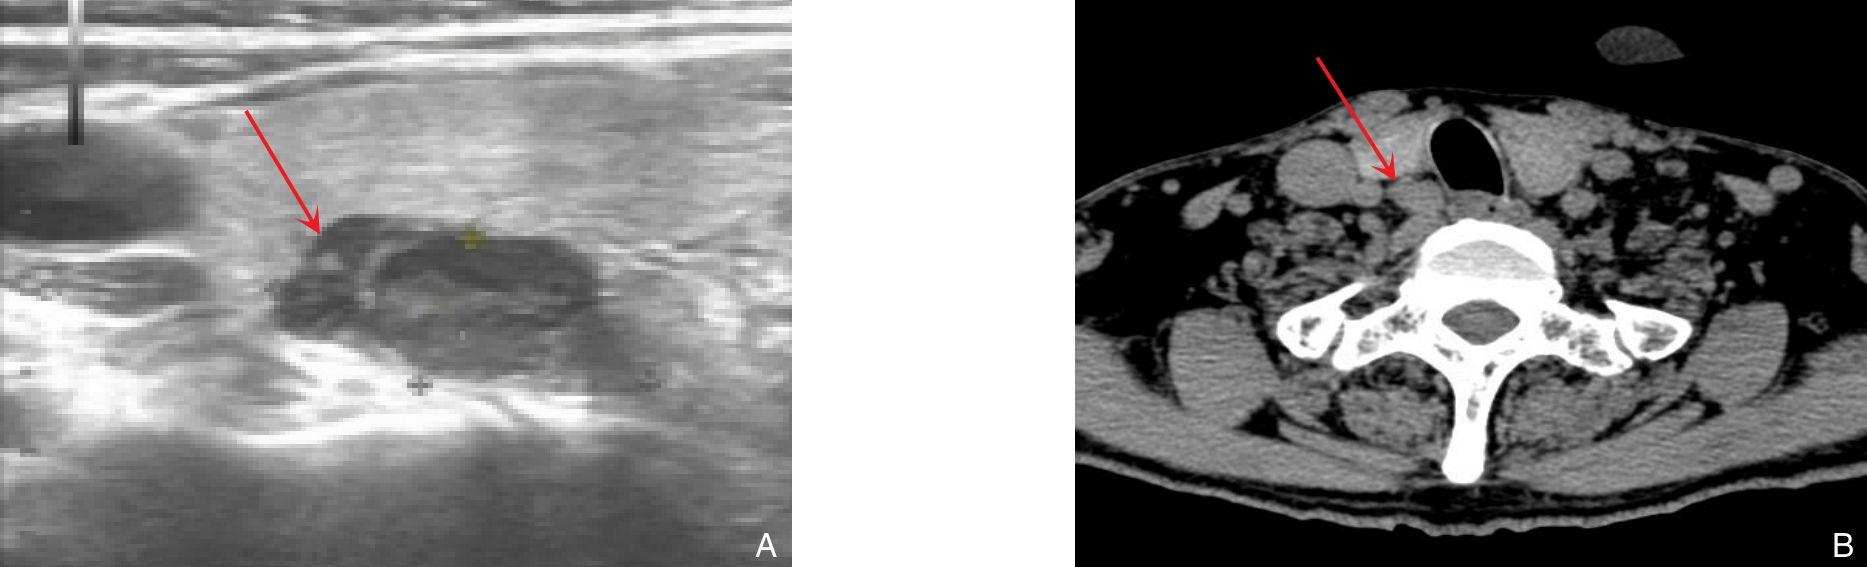

摘要:降钙素阴性甲状腺髓样癌(CNMTC)是一种少见的临床亚型,因术前血清降钙素水平正常,易导致漏诊或误诊。CNMTC的发病机制尚不完全明确,可能涉及分泌机制异常、测定假阴性等多种因素。目前,超声引导下细针穿刺细胞学检查、血清CEA与胃泌素释放肽前体水平、RET基因检测等在CNMTC的诊断中具有一定价值。治疗上,手术仍为首选方式,辅助以必要的新辅助治疗。本文通过系统回顾近年来相关文献,梳理CNMTC的发病机制、诊断路径、治疗策略及预后特点,以期为临床识别和管理该病提供参考。